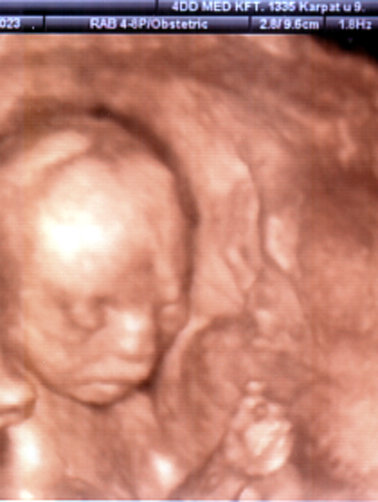

Anna 18 és fél hetesen: Kép Kép

Szóval elmentünk ide a géndiagnosztikára. Volt uh és kombinált vérteszt. Az uh-n minden rendben volt, 6,5 centi a CRL-je, hihetetlen hogy nyolc nap alatt majd két centit nőtt! Jó volt itt is a tarkóredő, ill. nézték az orrcsont meglétét, szerencsére az is rendben volt. A többi paramétere is korának megfelelő volt. Azért vicces hallani, hogy mondjuk 9 mm combcsont :)

A vérteszt is jó eredményeket hozott, 1:14000 (életkorom szerint 1:700) az esély Down-kórra és 1:115000 a többi kr. rendellenességre (korm szerint 1:5700). Úgyhogy nagyon biztattak minket, hogy rendben van a baba. Egyébként az uh-ról kaptunk dvd-t, még egy percnyi 4D is van benne :)